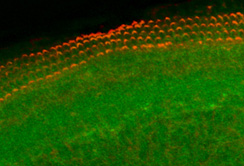

Innsbruck, 23.01.2012: In der Europäischen Union leben rund 44 Millionen Menschen mit einer Hörschädigung. Weltweit sind es annähernd 250 Millionen. Bis 2050 könnte die Anzahl der weltweit Betroffenen allerdings auf über 900 Millionen steigen, schätzt die WHO. Bisher sind viele Hörbeeinträchtigungen nicht therapierbar: Das Innenohr ist ein geschlossenes und schwer zugängliches Organ. „Schäden am Innenohr sind deshalb zur Zeit nur beschränkt therapierbar“, erklären Prof.in Anneliese Schrott-Fischer und Dr. Rudolf Glückert vom Forschungslabor für Innenohrbiologie der Innsbrucker HNO-Klinik. Durch die Zusammenarbeit von wissenschaftlichen und industriellen Partnern aus elf verschiedenen Ländern in dem Projekt „Nanoear“ konnten nun aber Nanopartikel entwickelt werden, die als Träger für Medikamente oder therapeutische DNA dienen. Diese können also gezielt an bestimmte Zellen ins Innenohr transportiert und dort freigesetzt werden. „Verwendet werden dafür Nanopartikel der dritten Generation, die in der Lage sind, verschiedene Moleküle aufzunehmen“, erklärt Prof.in Schrott-Fischer. „Noch sind die Partikel allerdings in einem Stadium, in dem sie nicht an Patient:innen angewendet werden können. Aber mit dem Projekt haben wir den Grundstock dafür gelegt, dass die Partikel weiterentwickelt und auch in der Praxis eingesetzt werden können.“ Es gibt daher die Hoffnung, mit Hilfe der Nanopartikel eine ganze Bandbreite von vielversprechenden neuen Therapiemöglichkeiten für die Behandlung von Hörbeeinträchtigungen zu entwickeln.

An dem Projekt „Nanoear“ haben insgesamt 14 Universitäten und zehn Firmen aus elf verschiedenen Ländern gearbeitet. Koordiniert wurde die Forschungsarbeit von der Universität Tampere in Finnland. Das von der EU finanzierte Projekt hatte ein Volumen von 10,5 Millionen Euro. Vom Forschungslabor für Innenohrbiologie in Innsbruck waren Dr. Rudolf Glückert, Mag. Christian Pritz, Dr. József Dudás, Dr. Soumen Roy und BMA Mario Bitsche unter der Leitung von Prof.in Schrott-Fischer an dem Projekt beteiligt. „Unser Beitrag war vor allem die Entwicklung eines Invitro-Modells, mit dem die entwickelten Nanopartikel an Zellen und Organkulturen getestet werden konnten“, sagt die Teamleiterin. Dadurch konnte die Auswirkung der Partikel auf das lebende Gewebe erforscht werden.